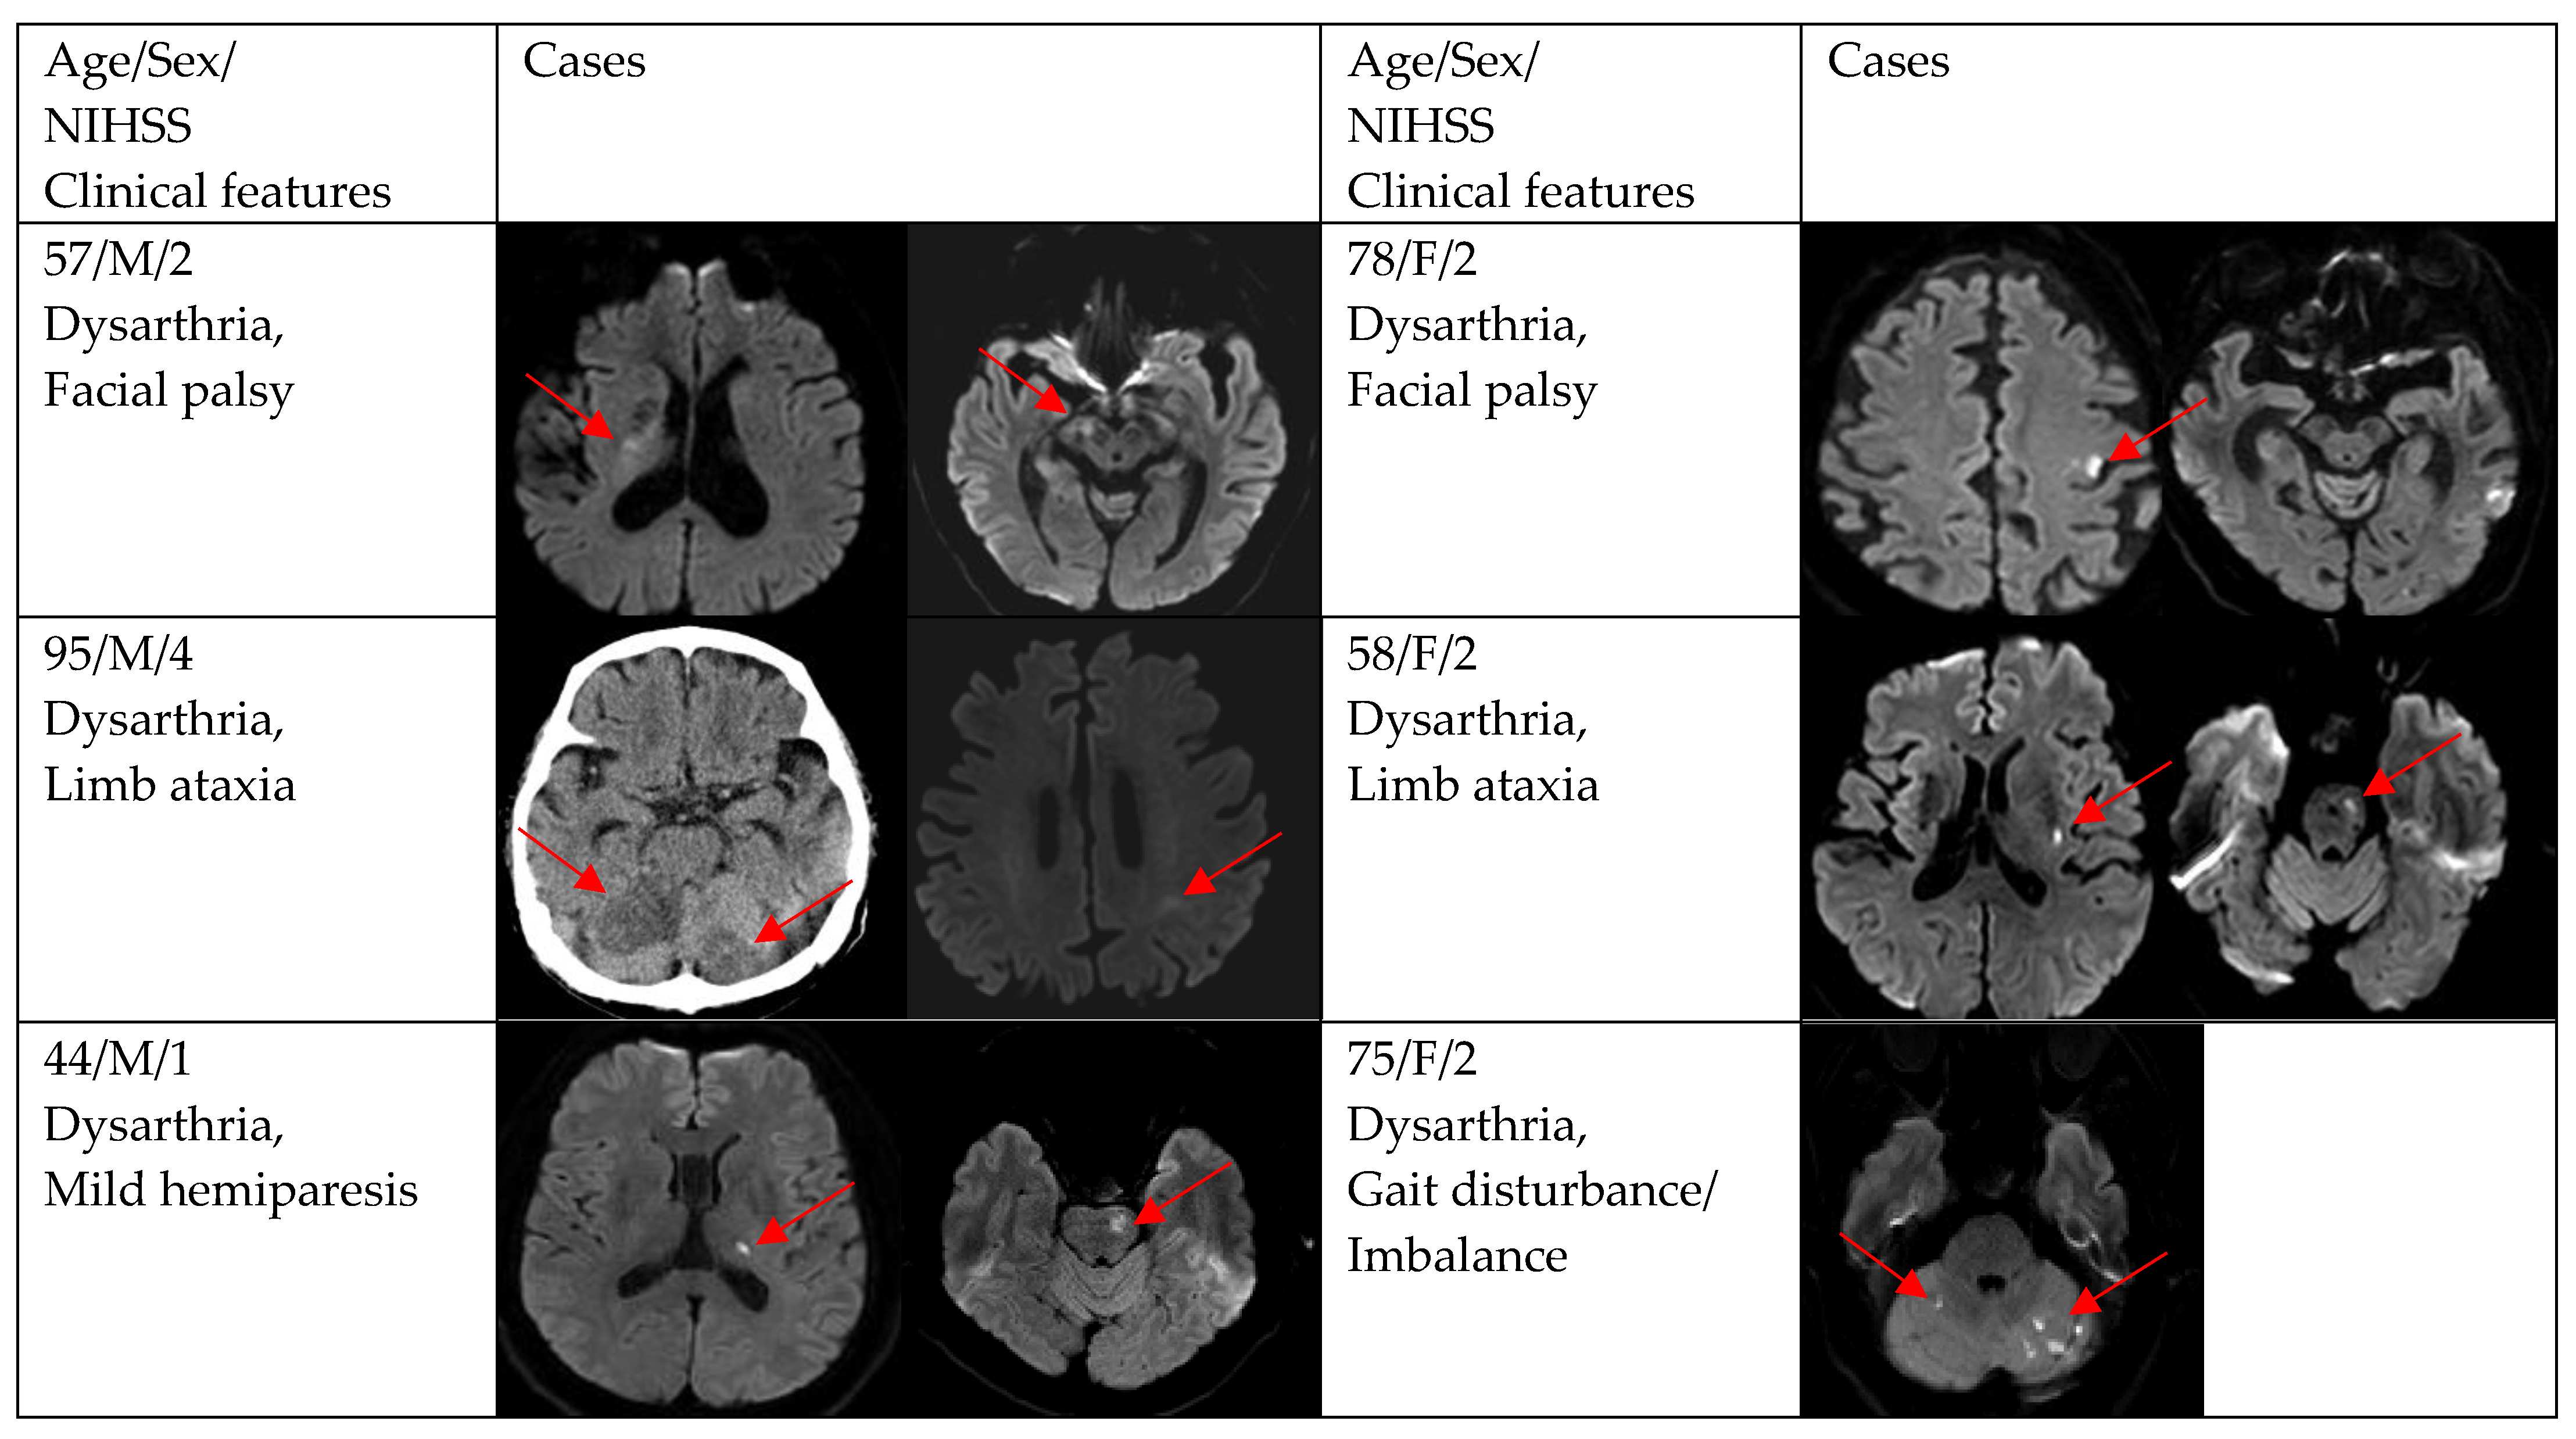

| Gait disturbance/imbalance | 9 (19.2) | 1 (7.7) | 8 (23.5) |

| Facial palsy | 8 (17.0) | 1 (7.7) | 7 (20.6) |

| Mild hemiparesis | 5 (10.6) | 2 (15.4) | 3 (8.8) |

| Limb ataxia | 3 (6.4) | 0 (0.0) | 3 (8.8) |